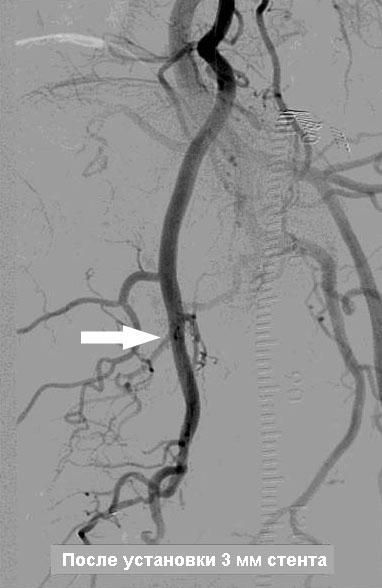

Если причиной эректильной дисфункции является недостаточный приток крови по артериям в половой член, то диагноз ставиться на основании специального исследования этих артерии – АНГИОГРАФИИ. В случае наличия сужений или закупорок в приводящих артериях, они четко видны на ангиограммах.

Мы исходим из фундаментального правила – устранить причину, а не лечить косвенным путем, как, например, действуют общеизвестные лекарства Виагра или Сиалис. В нашей клинике мы предлагаем современную и высококвалифицированную диагностику сосудистой системы таза и гениталий и, в случае наличия показаний (сужения или закупорки артерии), мы устраняем эту причину с помощью малоинвазивного (без хирургической операции) лечения – расширения суженных артерии и их внутрипросветного протезирования.

Как делается ангиопластика и протезирование артерии? . . .

После прокола артерии на бедре, в просвет сосуда вводится специальный зонд катетер, который подводится прицельно к артериям, кровоснабжающим половой член. После диагностики артерии и обнаружения сужения, в зону поражения артерии подводится миниатюрный баллонный катетер и сужение устраняется после раздувания баллончика. После сдувания и удаления баллона, на месте расширенного участка артерии ставится специальный каркас, который закрепляет результат и удерживает просвет артерии в раскрытом состоянии, нормализуя таким образом кровоток через расширенный и протезированный участок артерии. Указанная операция делается без общего наркоза и разрезов, только под местной анестезией с помощью маленького прокола (2-3мм) в бедренной артерии. В результате такого неинвазивного вмешательства нормализуется кровоток и, соответственно, нивелируется сосудистая причина эректильной дисфункции.